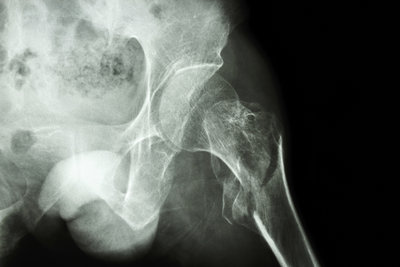

Die häufigsten Ursachen für Hüftschmerzen und Knieschmerzen sind abnutzungsbedingte Veränderungen des Gelenkes sowie auch unfallbedingte Verletzungen  (Knie- und Hüftverletzungen) und Verletzungsfolgen wie beispielsweise Hüftarthrose, Kniearthrose, gelenknahe Knochenbrüche, Meniskusrisse, Kreuzbandrisse.

Behandlungen von Hüft- und Kniegelenksverletzungen und degenerative abnutzungsbedingte Leiden sind eine unserer Spezialitäten, so zum Beispiel Kunstgelenkersatzoperationen an Hüfte und Knie, als auch Knochenbruchbehandlungen insbesondere hüftgelenksnahe Frakturen, Oberschenkelbrüche oder auch Knochenbrüche unter Mitbeteiligung des Kniegelenkes. Eine unserer weiteren Spezialitäten ist die Behandlung von Meniskus- und Kreuzbandrissen. Die Entwicklungen auf diesem Fachgebiet sind enorm vorangeschritten, sodass heute viele Eingriffe in entsprechender arthroskopischer oder minimal-invasiver Technik durchgeführt werden können. Dies führt in der Regel zu bedeutend kürzeren Spitalaufenthalten. Für weitere Informationen wenden Sie sich an unsere Praxis, kontaktieren uns via Kontaktformular oder entnehmen Informationen aus den nebenstehenden Links. Doch was ist eigentlich Arthrose? Lesen Sie auf diesem Link weiter!